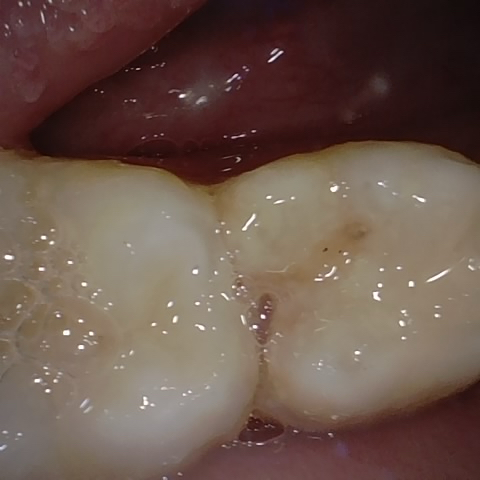

Annotated as "Good"